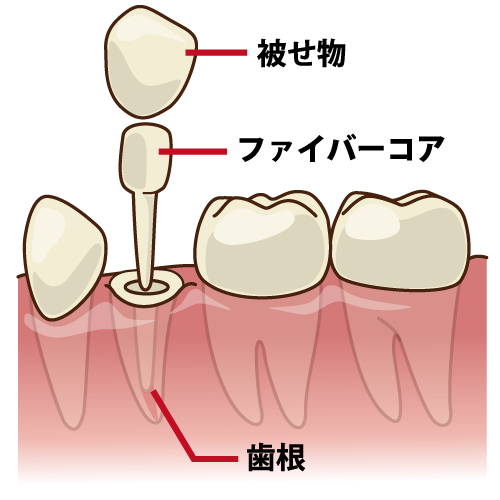

ファイバーコア

歯の破折を防ぐ「しなやかな土台」

根管治療後の歯を補強するための心棒(土台)です。

グラスファイバーの繊維を束ねた素材を使用します。

従来の金属の土台(メタルコア)は硬すぎて、強い力がかかった時にクギのように歯の根を割ってしまうことがありました。

ファイバーコアは歯に近い「しなり」があるため、衝撃を分散し、大切な歯が割れるのを防ぎます。

だからこそ、当院では「ファイバーコア」で補強し、マイクロスコープを用いた精密な「被せ物(審美歯科)」を行うことで、折れにくく長持ちする歯に仕上げます。